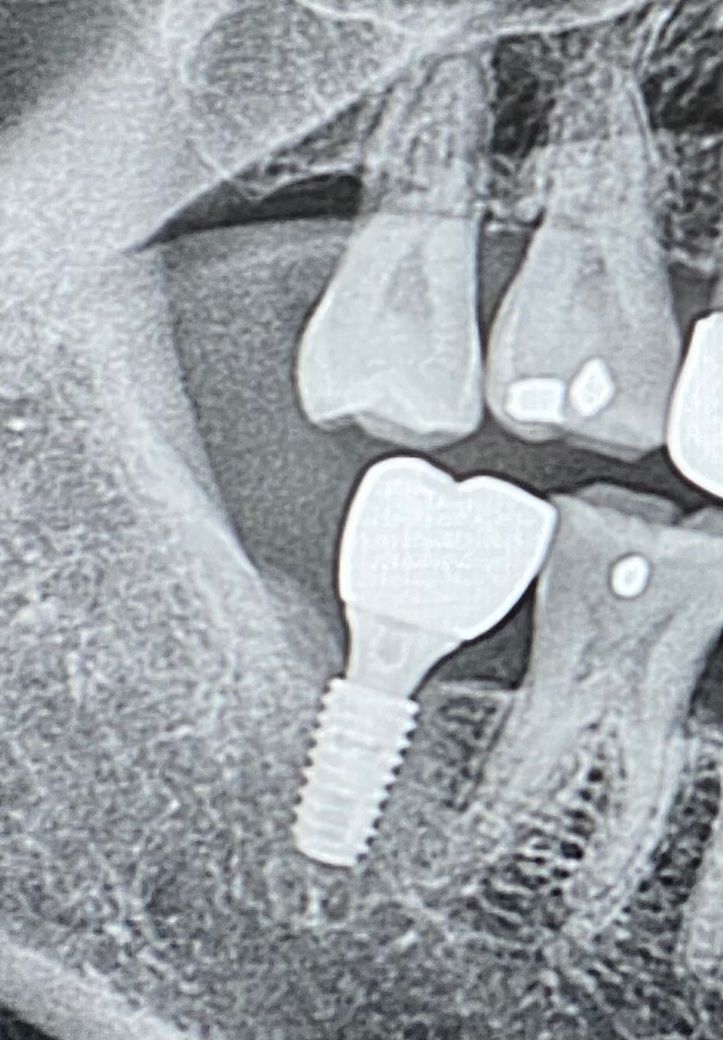

임플란트 대합치 정출 갈아서 교합 맞출 수 있나요??

임플란트 하고 대합치 정출로 교합이 이상해요

병원에서 임플란트 크라운은 무상으로 재제작 및 정출치아 갈아서 교합 맞춰준다는데 위쪽 치아 얼마나 갈아낼수 있나요??

엑스레이상 갈아낼수 범위가 있나요??

아니면 일반 치아의 갈아낼수 있는 범위가 있나요??

자연치아를 갈아낼때에는 1미리미터 정도는 갈아낼 수 있습니다. 그 이상은 신경치료 가능성이 높습니다.

자연치아를 갈아서 맞추는 건 1~2mm 정도입니다 그 이상은 치수가 간접적으로 노출되어 치아가 시릴 수 있습니다